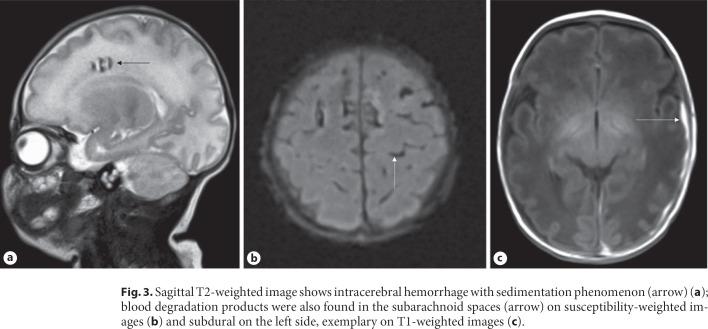

Current evidence from the COVID-19 pandemic suggests that neonatal SARS-coronavirus-2 infections usually have a mild course. Data on how maternal infection during pregnancy affects fetal development are scarce. We present the unique case of a moderate preterm infant with intracranial bleeding and periventricular leukomalacia as a potential consequence of post-COVID-19 hyperinflammation during pregnancy.

目前来自 COVID-19 大流行的证据表明,新生儿感染 SARS-CoV-2 通常呈轻度病程。关于母亲在怀孕期间感染新冠病毒如何影响胎儿发育的数据很少。我们报告了一例独特的中度早产儿病例,其颅内出血和脑室周围白质软化可能是妊娠期间 COVID-19 后过度炎症的结果。